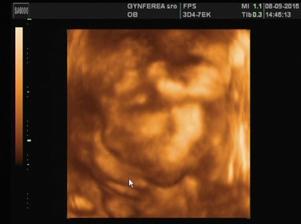

Naše vymodlené ♥

@lenkato7 áno od 20. 5. keď bilo srdiečko to je potvrdené a radujem sa najviac na svete 🙂 ďakujem a dúfam že sa čoskoro pridáš ♥

@anonymmb jeeej zlatá si ♥ áno 6. 1. mám termín 🙂 a prišlo to presne vtedy keď sme najmenej čakali 🙂